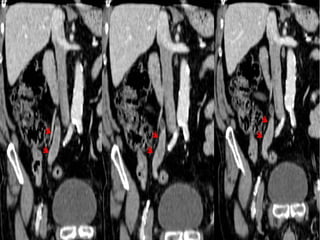

• #15 DISPLASIA UROTELIAL. Imágenes axiales de TCMD realizado en fase nefrográfica (A) y en fase excretora (B) que muestran la presencia de dos pequeñas proliferaciones papilares en la pared antero-superior de la vejiga urinaria (flechas y punta de flecha).

• #16 DISPLASIA UROTELIAL. A) Imagen axial e imagen coronal (B) por TC que muestran las pequeñas proliferaciones papilares. CARCINOMA UROTELIAL papilar con FENOTIPO PLASMOCITOIDE. La ecografía (A,B) muestra una ocupación de la luz vesical por una tumoración sólida de aspecto sésil.